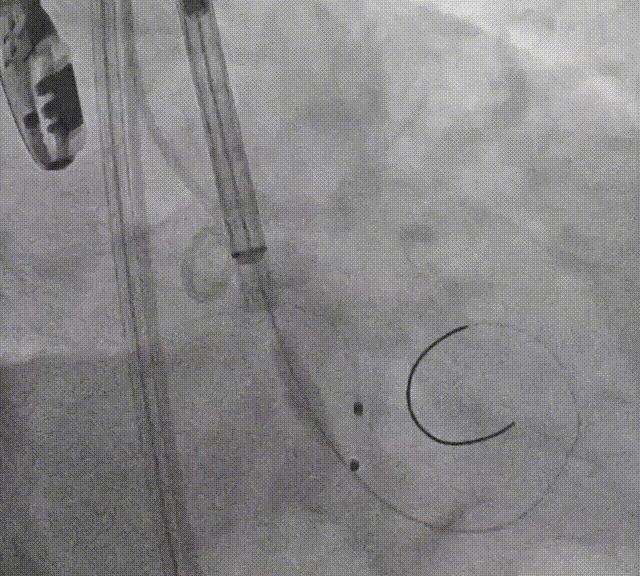

导丝跨瓣

主动脉根部造影